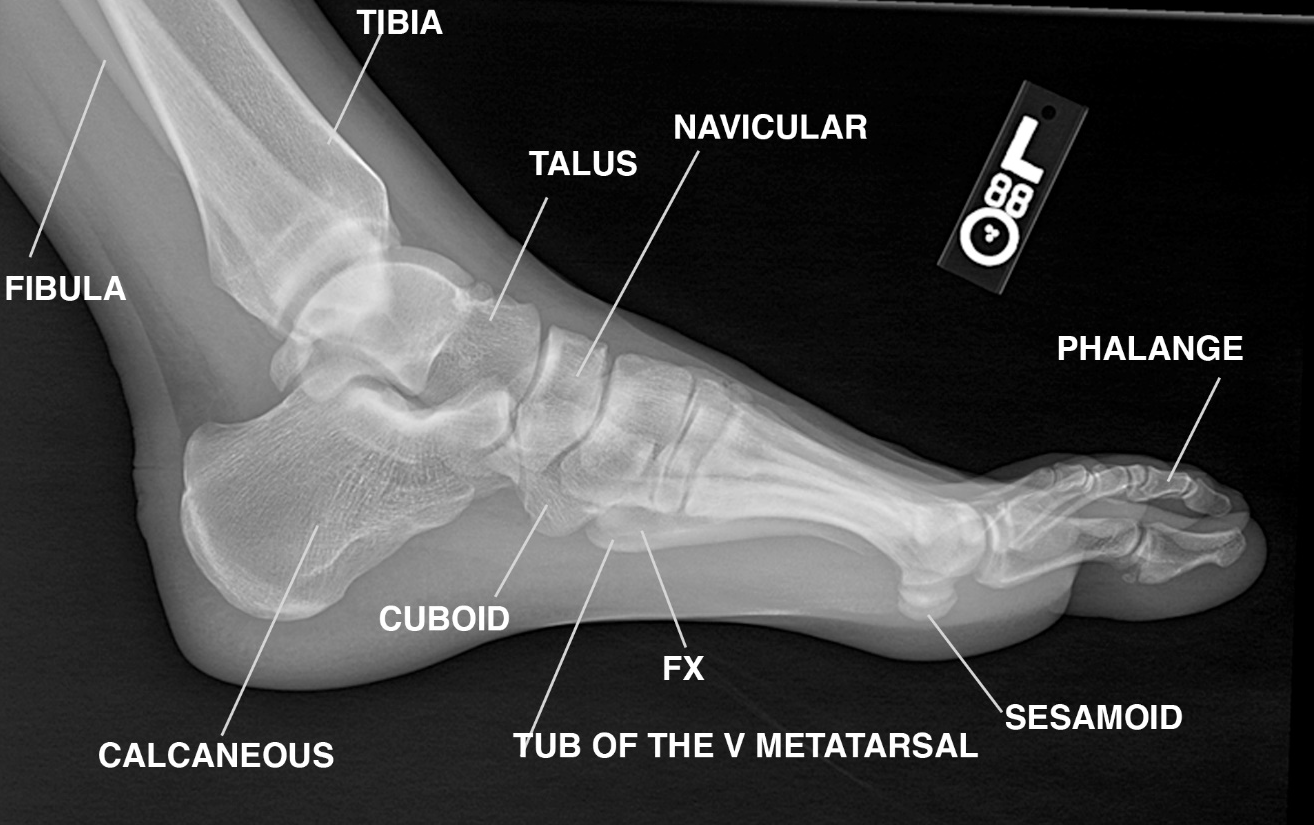

Ankle Bones Names and Anatomy With Labeled Diagrams

Ankle Bones Names and Anatomy With Labeled Diagrams Foot Bones Protruding These growths may be uncomfortable to walk or stand on and might be unpleasant. Learn to fix the pain today! Bony outgrowths that form on the foot’s bones are referred to as bone spurs or osteophytes. They form when a joint or bone has been. Osteophytes (bone spurs) are bony lumps that grow on the bones in the spine or. Foot Bones Protruding.